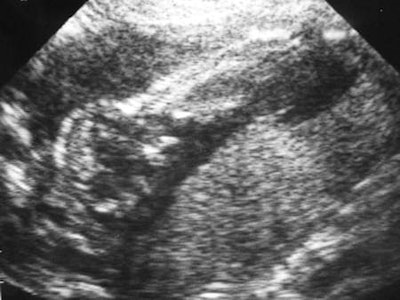

Ultrasound has changed the perception of the fetus. Images like this one taken in 1985 have a powerful social meaning, and for many people are the first cherished pictures of a child.By 1969, ultrasound techniques were established, but it took many years for radiologists to fully embrace the technique. The attitude of radiologists is now difficult to understand when the importance of ultrasound in radiology departments is obvious. Donald was an introduction to the theme in 1975 when he said that, "Sonar indeed employs a different energy spectrum from that of roentgenology and the information yield is consequently different, but the whole ever-increasing science and art of existing visual diagnostic techniques can now embrace new horizons by adopting sonar not as a rival but as a complementary discipline. Whether the world of radiology likes it or not, it will assuredly come to recognize and meet the challenge in the future."